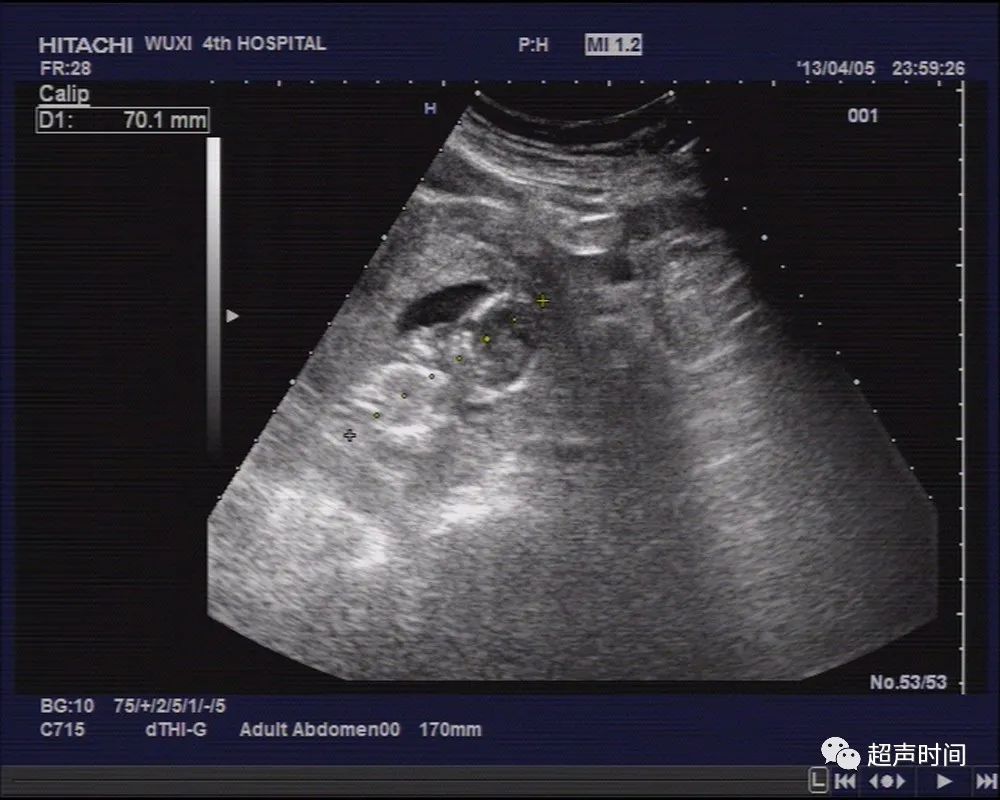

膀胱充盈可,子宫前位,稍大,肌层回声尚均,宫腔内未见明显孕囊结构,宫腔内可见低回声区,双卵巢显示不清,于左侧盆腔探及一类似妊娠囊结构,周边回声稍增强,其内可见一胎儿回声,头臀长约 71mm ,可见胎心、胎动(图 1~ 2 )。

图 1 左侧盆腔探及一类似孕囊结构,内见一头臀长约 70mm 的胎儿回声